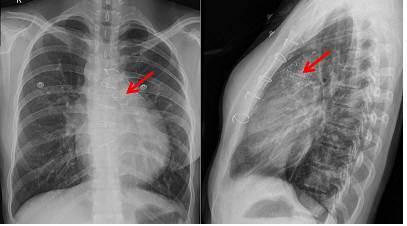

인공심장 판막이 폐동맥 판막 부위에 이식된 사진

국내 의료진이 국산 기술로 개발한 폐동맥 인공심장 판막으로 환자 10명을 치료하는 임상시험에 성공했다.

19일 서울대병원에 따르면 김기범 서울대병원 소아청소년과 교수팀(사진)은 1개당 가격이 수천만원에 달하는 인공심장 판막을 지난해 2월 사람 10명에 이식하는 첫 임상시험을 실시했다. 수술 후 현재까지 별다른 부작용이 없었다.

김 교수팀에 따르면 ‘폐동맥 인공심장판막’은 돼지의 심장 외막을 이용해 만들었다. 폐동맥 인공심장 판막은 우심실이 폐동맥으로 혈액을 뿜어낼 때 다시 우심실로 역류하는 것을 막아주는 기능을 한다. 하지만 판막에 문제가 생기면 혈액 역류 현상으로 피를 뿜어내는 심장 펌프기능에 저하된다.

그 결과 펌프기능이 약해지면서 심장이 신체 곳곳으로 혈액을 충분히 공급하기 어려워진다. 이에 인공심장 판막을 이식해 치료하고자 한 것. 이 임상시험에 참가한 판막질환 환자를 추적 관찰한 결과, 면역거부반응이 나타나지 않았다.

면역거부반응을 최소화한 방법에 대해 김 교수팀은 “인공판막은 소나 돼지의 심장 조직으로 만든 판막을 특수면역처리를 해서 만들었다”며 “이번에 개발한 판막은 돼지의 심장조직에 남아있는 세포를 제거하는 탈세포화 조직처리를 했고, 사람과는 달리 돼지 등 포유류에 많고 조직반응을 주로 일으키는 주범으로 알려진 ‘알파갈’이라는 단백질을 제거했다”고 설명했다. 심장 내 역류 현상도 거의 사라졌다. 우심실의 부피도 평균 32.1%나 줄었고 합병증도 나타나지 않았다.